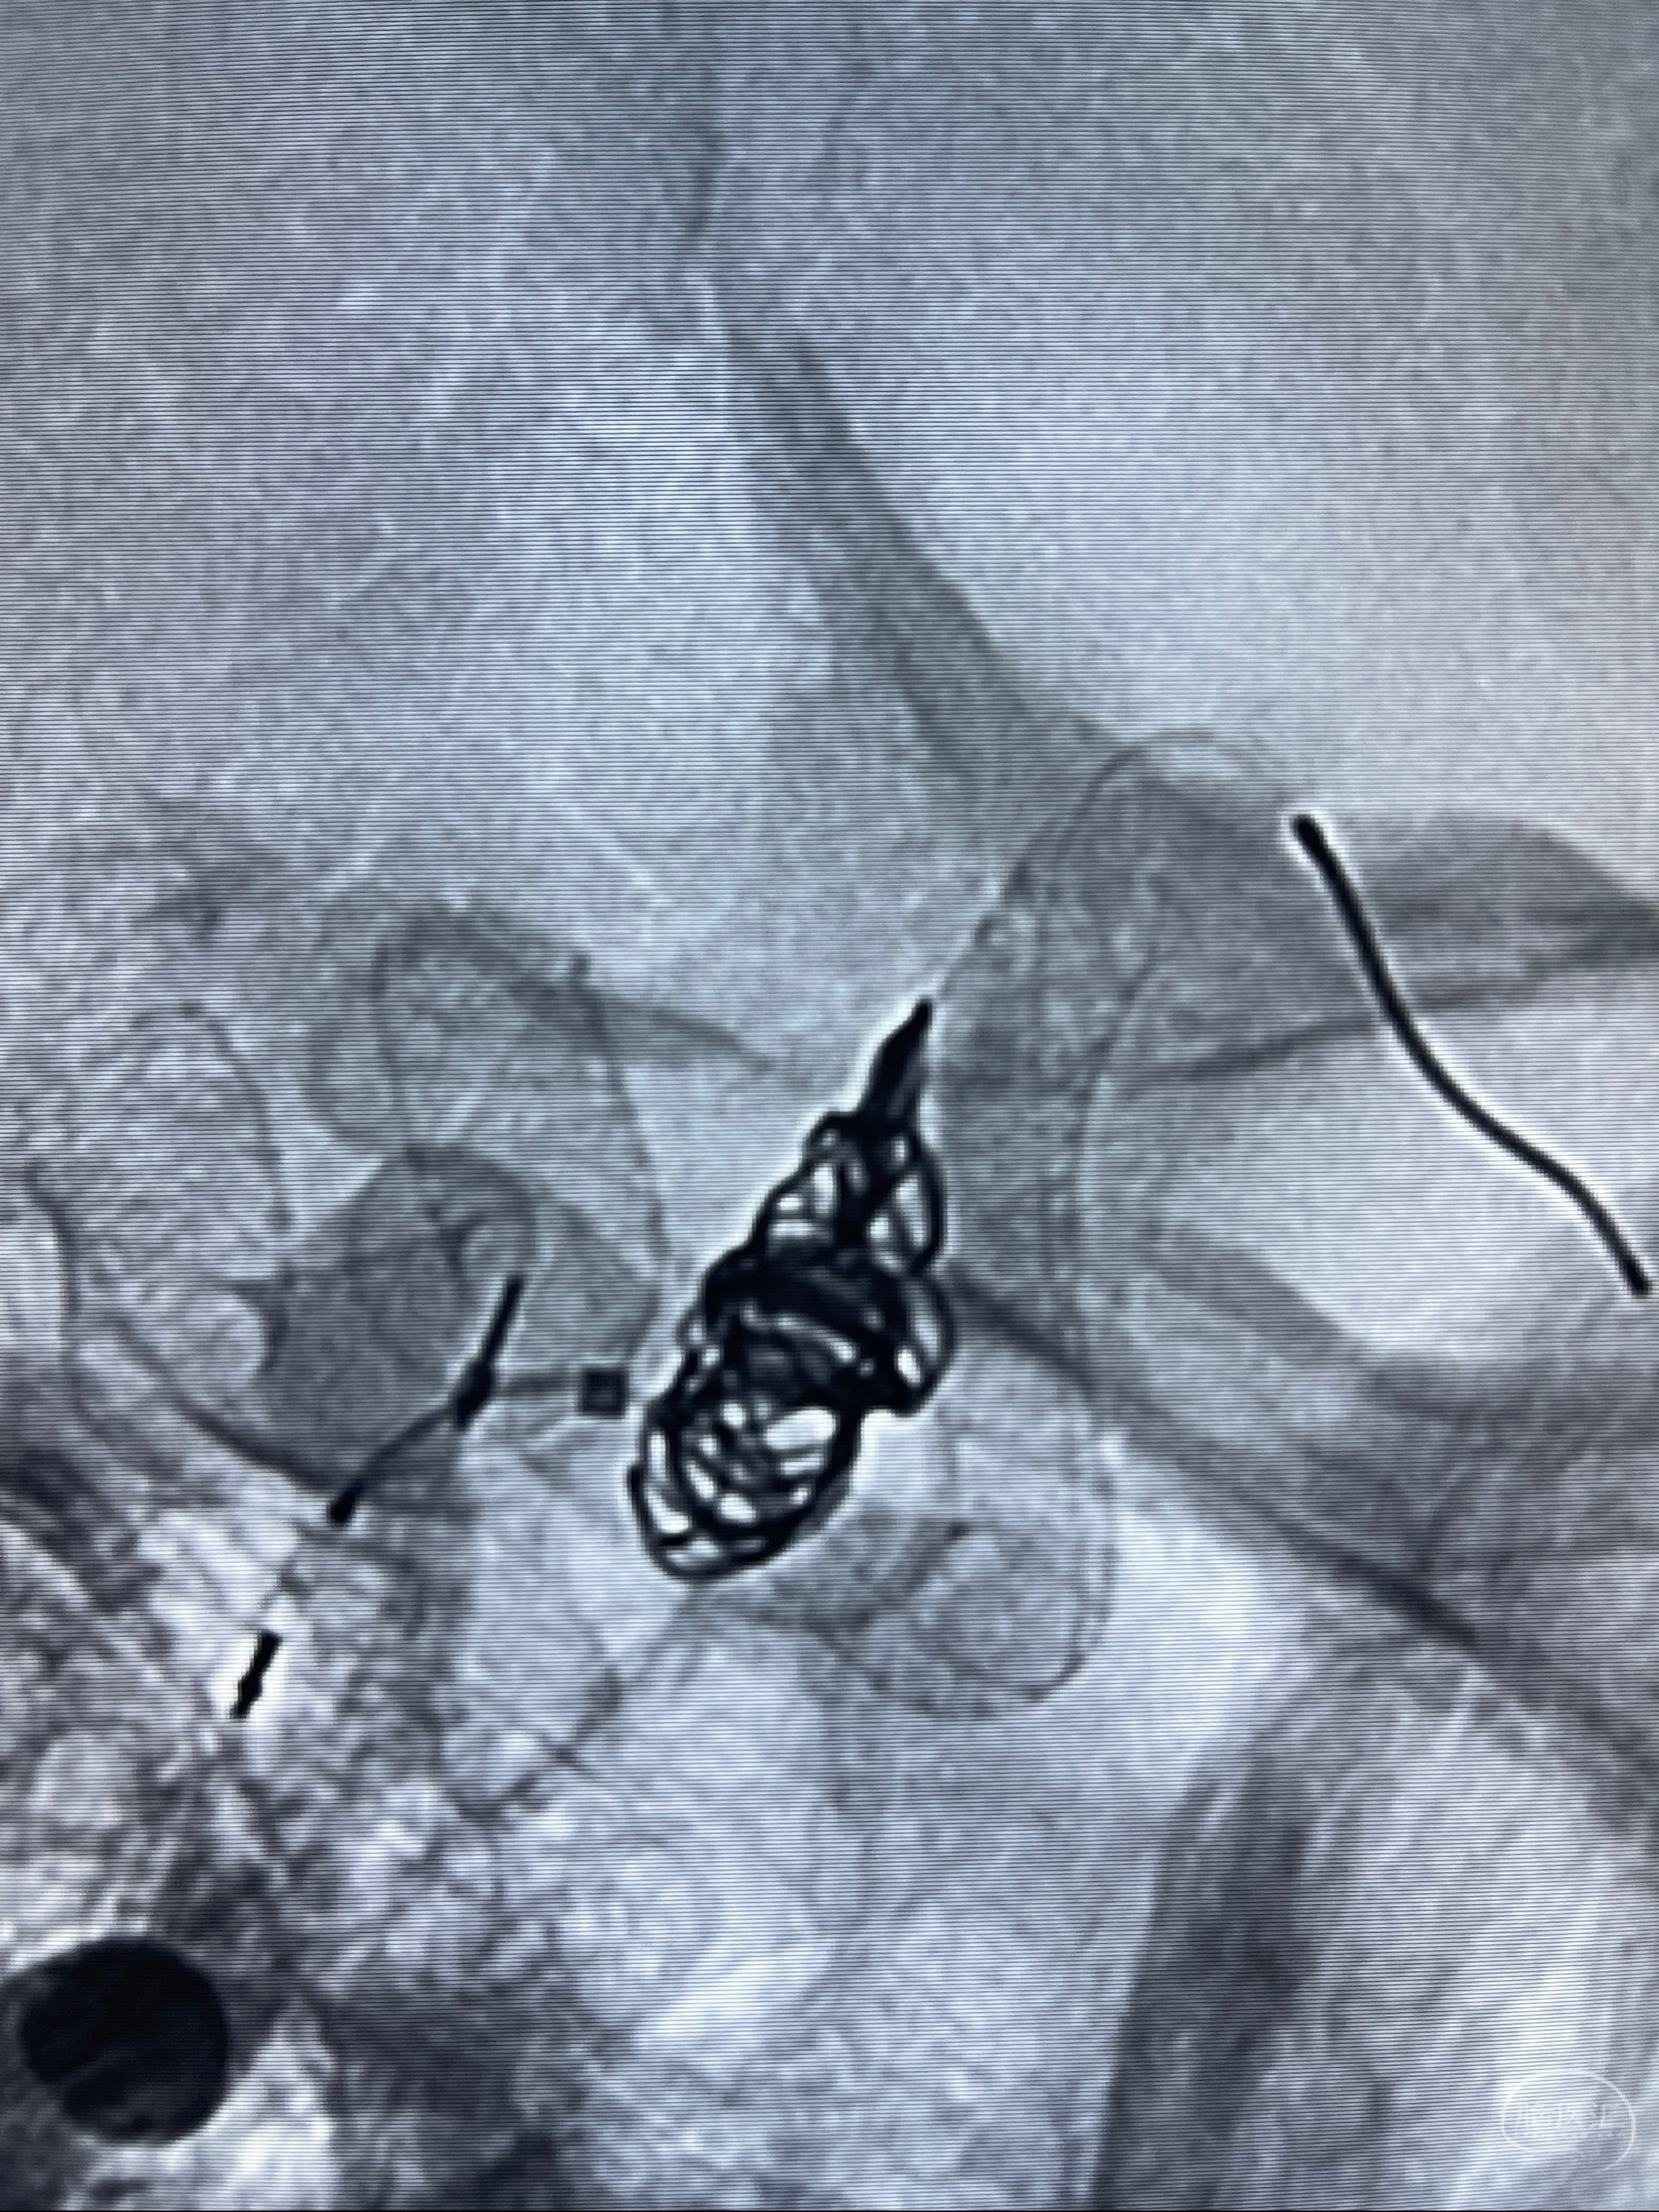

2023-07-27全脑血管造影:双侧颈内动脉眼动脉段动脉瘤,右侧较大

2023-08-01全麻下行双侧颈眼动脉瘤支架辅助栓塞

- pipeling4.5-20mm

- pipeline 4.0-20mm

术后即刻CT